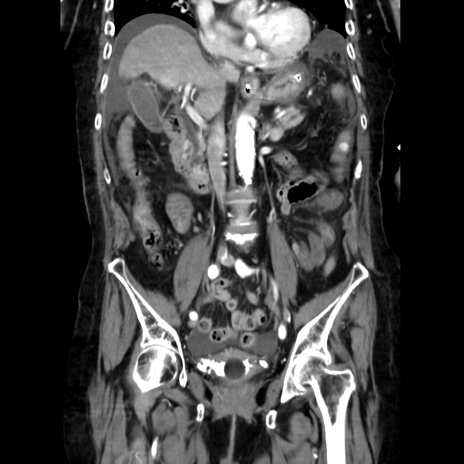

症例40(冠状断像)

冠状断像